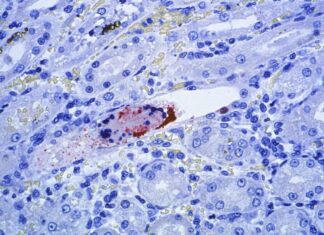

Nipah: vírus sem vacina e com alta letalidade acende alerta sanitário na Ásia

Identificado em 1999, o vírus Nipah voltou a acender o alerta das autoridades de saúde nas últimas semanas após a confirmação de novos casos...

Surto de vírus letal na Índia atinge profissionais de saúde e acende alerta sanitário

Autoridades de saúde da Índia entraram em alerta após a confirmação de cinco casos do vírus Nipah no estado de Bengala Ocidental. Todos os...